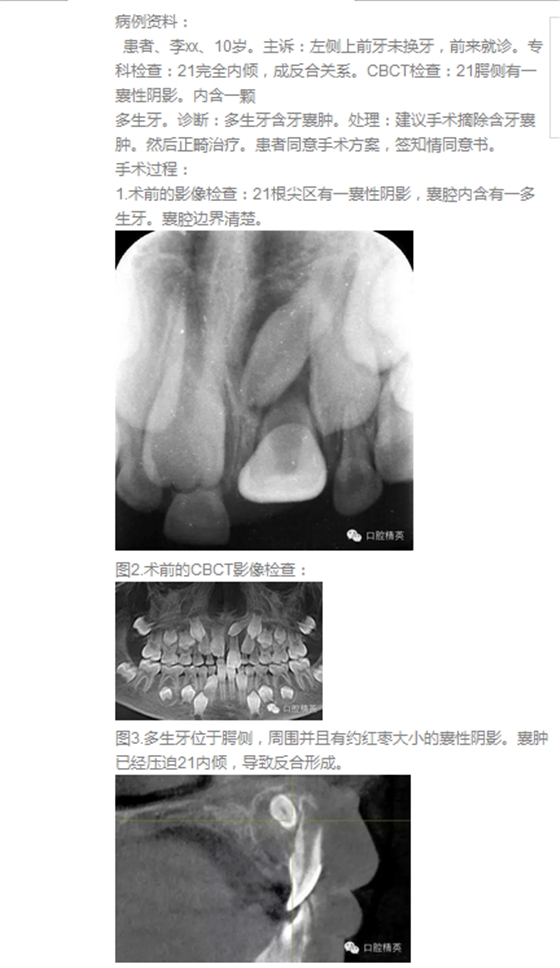

首頁口腔外科 高難度含多生牙囊腫的摘除

高難度含多生牙囊腫的摘除